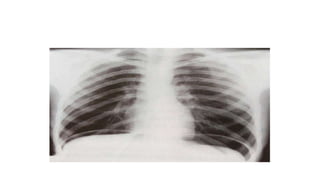

A normal chest x-ray shows the lungs, heart, bones, and soft tissues appearing healthy and unobstructed. The document discusses the different views used in chest x-rays, including PA, AP, lateral, and lateral decubitus views. It also covers topics like depth of inspiration, rotation exposure, the lobes of the lungs, identifying the heart, and how to read a normal chest x-ray.